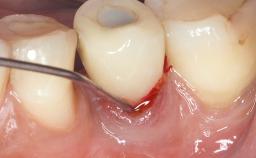

Reconstructive Treatment of a Peri-Implantitis Defect at an Implant in a Mandibular Molar Site

In this case, Mario Roccuzzo utilizes surgical bone regeneration treatment around implant 46 using a bone graft substitute and a connective tissue graft to resolve peri-implant inflammation, reduce the probing depths, and prevent further progression of disease.